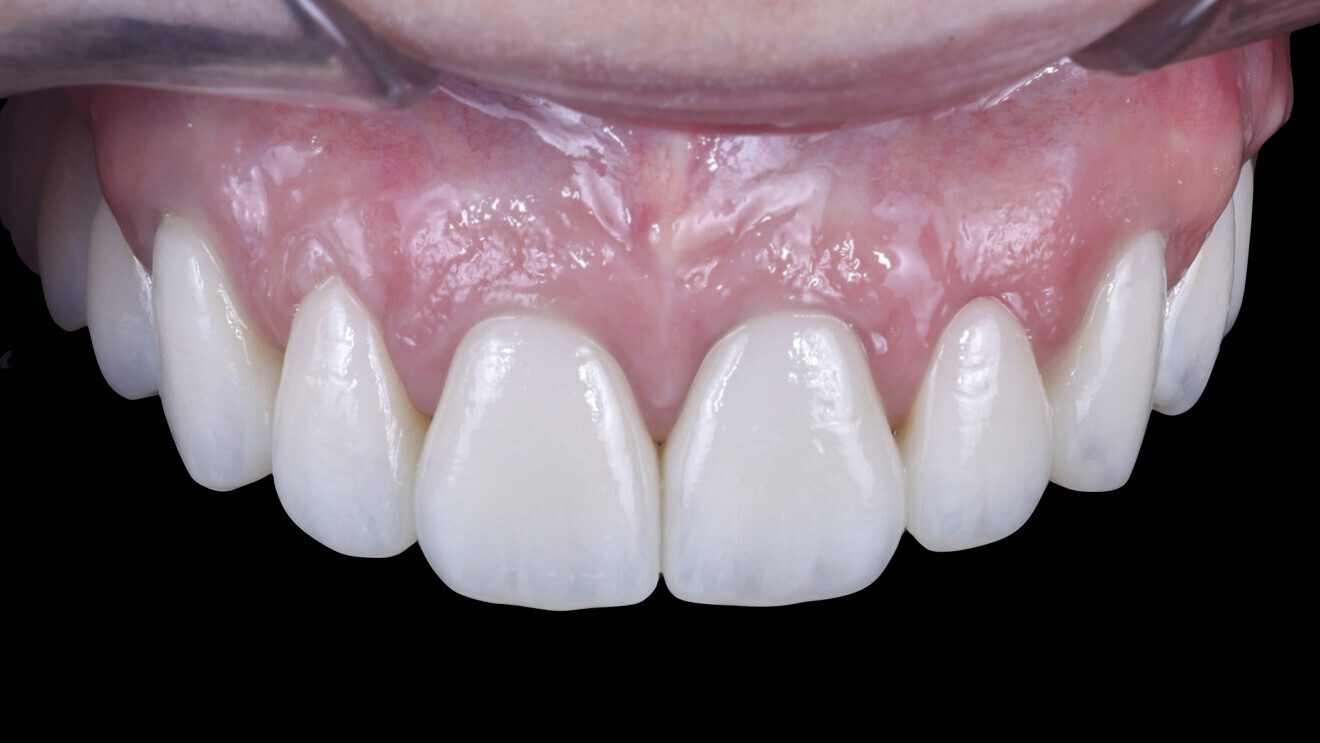

3. Soft-tissue aesthetics and passive fit: The most important aspect in this case was the appearance of the soft tissue. Upon insertion of the definitive restoration, we achieved a perfect result and no blanching of the gingivae, indicating proper tissue support. Furthermore, there was no tension upon insertion, ensuring a comfortable fit and long-term stability of the zirconia restorations (Figs. 33–35).

Figs. 33 & 34: Appearance of the papillae on the day of cementation.

Fig. 35: Definitive restoration in place.

This design strategy, combining precision in planning and soft-tissue management, resulted in a highly aesthetic and functional definitive restoration (Figs. 36a–37b).